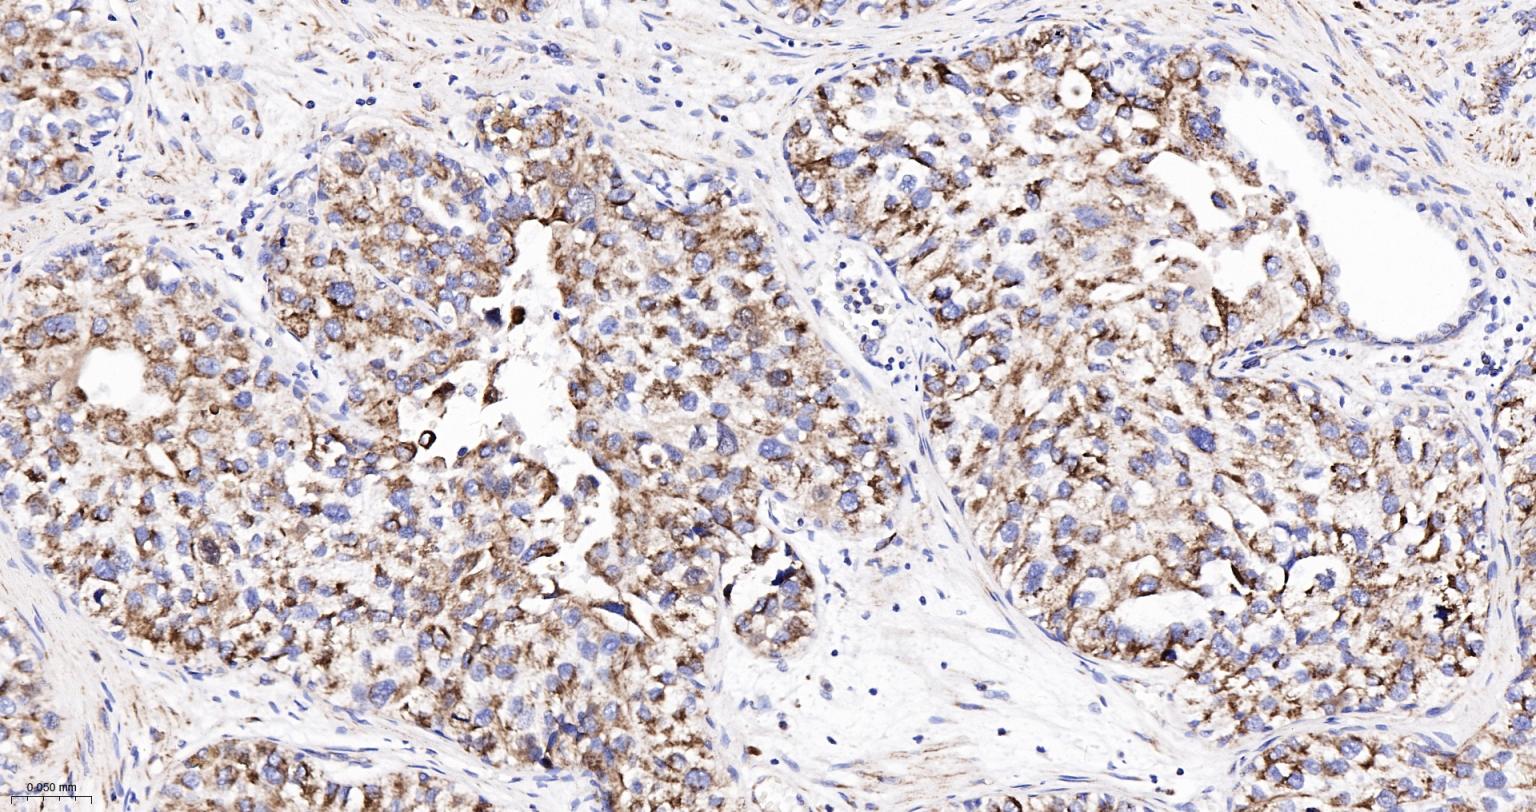

Paraformaldehyde-fixed, paraffin embedded Human Colon Cancer; Antigen retrieval by boiling in sodium citrate buffer (pH6.0) for 15 min; Antibody incubation with Cytochrome C Monoclonal Antibody, Unconjugated(bsm-52050R) at 1:200 overnight at 4°C, followed by conjugation to the SP Kit (Rabbit, SP-0023) and DAB (C-0010) staining.